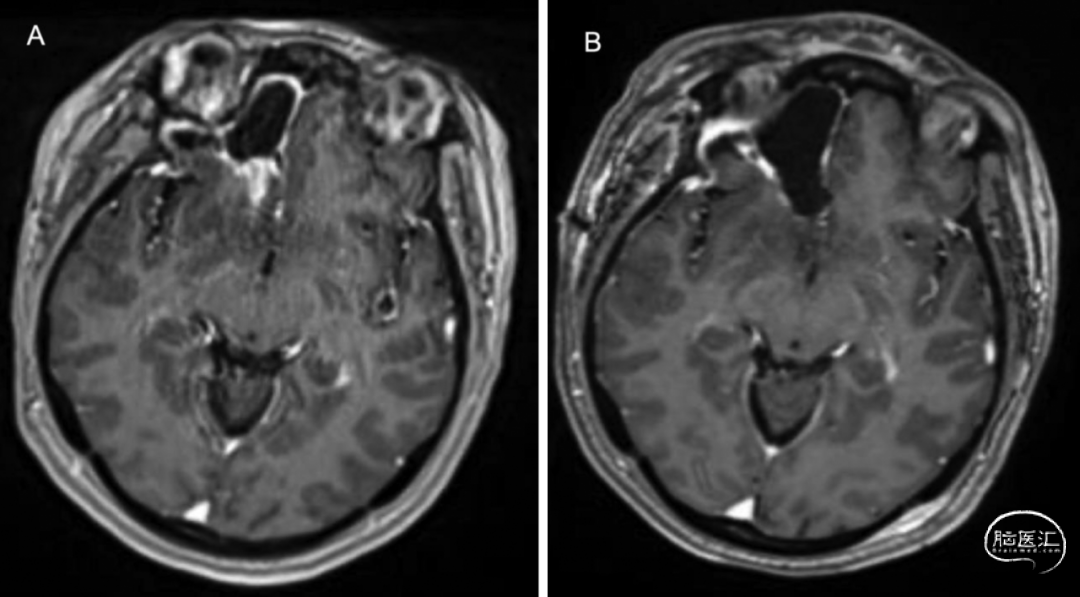

● 患者为34岁女性,其母亲的两位姐妹均有乳腺癌和结肠癌病史。她因持续头痛就诊,头痛在早晨尤为严重,常常干扰睡眠。脑部MRI显示右侧额叶前部有一个3.5×3.0cm的病灶,呈斑片状强化(图1A)。

1.初次手术:患者接受了右侧开颅手术,切除的肿瘤质地较硬,类似低级别胶质瘤。患者在术后第3天顺利康复出院(图1B)。

图1. A:初次术前MRI检查,显示右侧额叶内有一个不均匀强化的病灶;B:初次术后初期MRI检查,显示右侧额叶内的肿瘤已完全切除。

4.二次手术:术后1年随访MRI,显示肿瘤复发(图3A)。患者接受再次切除手术,术中使用了5-氨基酮戊酸(5-ALA)但术中并未观察到荧光,这进一步突显了该肿瘤的非典型性(高级别胶质瘤中可见荧光阳性)。实现完全切除,术后第4天出院(图3B)。病理检查显示其组织学特征与原发肿瘤一致,但Ki-67增殖指数从2%~5%上升至15%~20%。

图3. A:初次术后1年随访MRI,显示肿瘤复发;B:二次术后MRI,显示病灶切除。